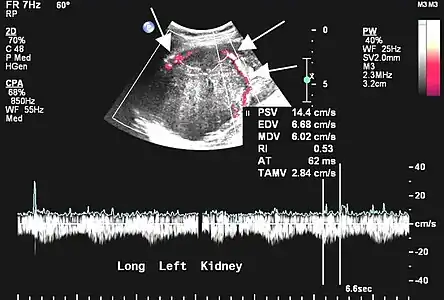

- Tumeur fibreuse solitaire du rein

Aspect échographique. La vascularisation est visible en rouge, repérée par les flèches[46].